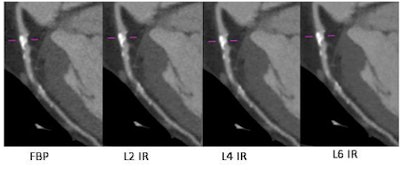

A 54-year-old man with a body mass index of 26.9 underwent coronary CT angiography using a step-and-shoot protocol (140 mAs, 225 mAs, DLP 342.3). In images reconstructed using FBP (left) and various levels of iterative reconstruction (IR) with iDOSE 4 (Philips Healthcare), noise reductions can seen in the IR images (right), but attenuation and plaque volumes are essentially unchanged. Images courtesy of Dr. Richard Takx.But while iterative reconstruction is implemented more and more in practice, there are little data assessing the effect of different levels of iterative reconstruction on the detection and characterization of noncalcified plaques, he said.